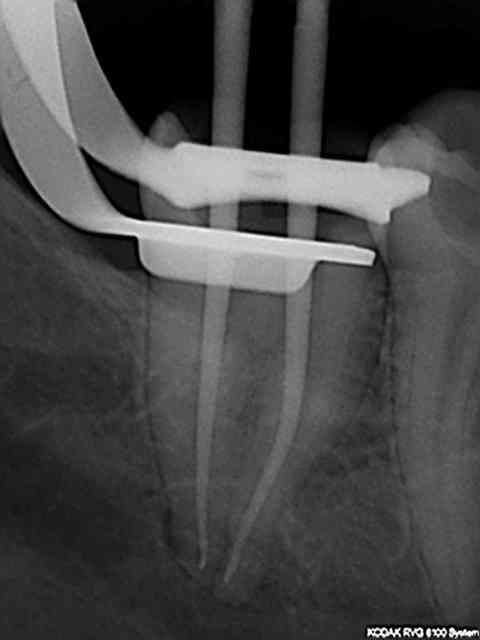

sinon ce matin essai nouvelle séquence: R25,largo N°3, r25, S1 sur endomaster pour la lt, r25. Encore plus rapide. Mais bon seulement 2 canaux boulevards.